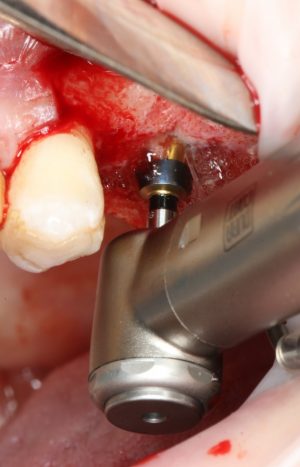

Приступаем к установке имплантата.

Кстати, комплект поставки не содержит ни заглушки, ни абатмента. А сам имплантат фиксируется на ключе простым заклиниванием платформы. Т. е. не слишком надёжно:

По этому поводу существует поговорка: «Кто не ронял имплантаты Astra Tech, тот не работал с имплантатами Astra Tech«. В общем, будьте аккуратны, в идеале, проводите все манипуляции по фиксации имплантата на ключе над столом.

Если лунка подготовлена правильно, то имплантат проваливается в неё почти полностью:

и докручивается до правильного положения несколькими оборотами.